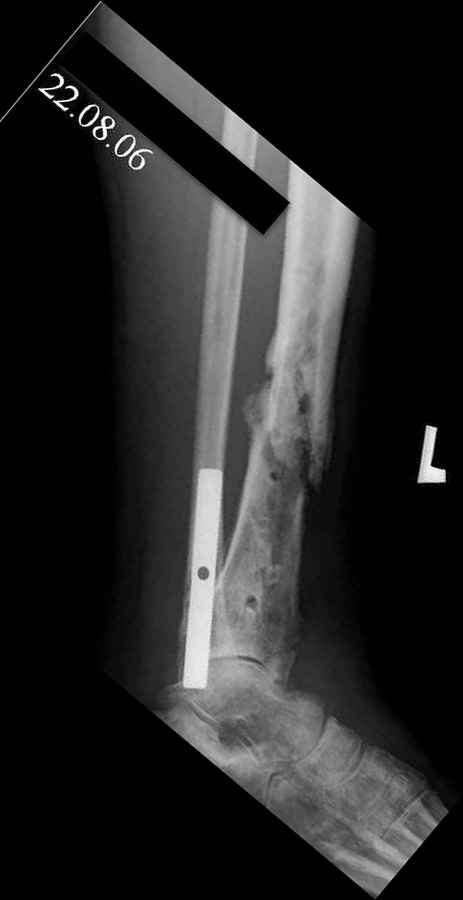

Re: Дефект и остеомиелит tibia